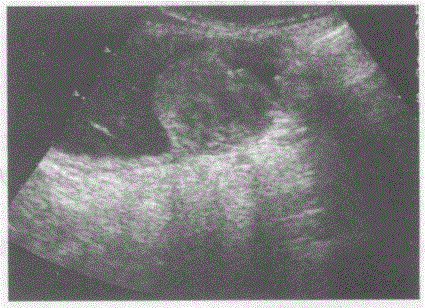

临床资料:男,59岁,自诉剑突下疼痛、不适半年余。超声综合描述:饮水后扫查胃大弯处可见不均质中等回声,向腔内突起,表面不平,胃壁层次不清。超声...

问题 临床资料:男,59岁,自诉剑突下疼痛、不适半年余。 超声综合描述:饮水后扫查胃大弯处可见不均质中等回声,向腔内突起,表面不平,胃壁层次不清。 超声提示:

选项 A.胃息肉 B.胃溃疡 C.胃癌 D.胃脂肪瘤

答案 C